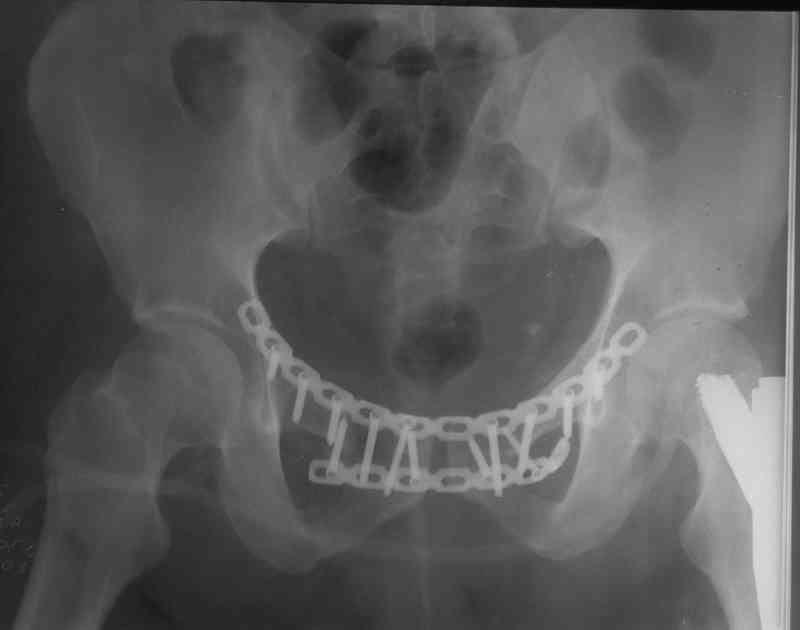

Пластина спереди (на лонные кости) открыто и каннюлированные винты с обеих сторон сзади - закрыто.

Предварительная репозиция может быть достигнута при помощи аппарата.